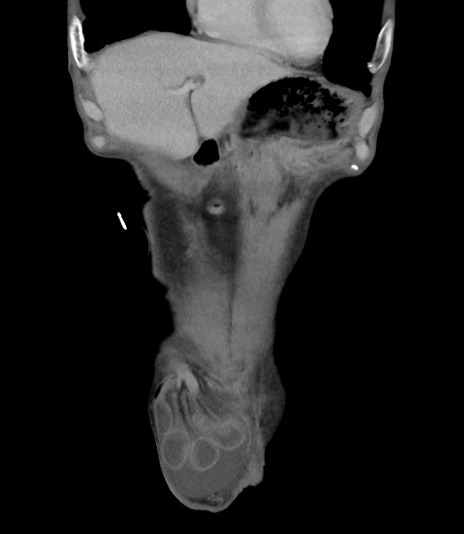

横断像

矢状断像